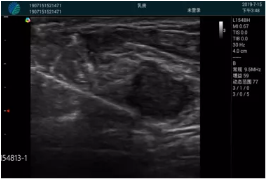

清晰顯示腺體內(nèi)低回聲快影,邊界清晰,包膜較光滑

腺體內(nèi)部清晰顯示一低回聲塊影,形態(tài)不規(guī)則,邊界模糊,邊緣呈毛刺狀,內(nèi)部見砂礫樣鈣化